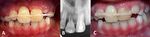

planted six permanent upper incisors. Protocols for replan-        immobilized by a rigid metal splint (fig. 1-A, B). Tooth 11

tation are performed by oral surgeons. Pediatric dentists and      was replanted in infra occlusion compared to tooth 21 ac-

endodontists take the postoperative dental care and con-           cording to an old radiograph (fig. 1-C). Antibiotics were

trol the follow up period. Presented clinical cases are fol-       prescribed to the patients.

Fig. 1. A.I.,11 years old girl. A) OPG after replantation and splinting of teeth 11, 21. B) there is a disparity in the

level of incisor‘s cut edges between replanted teeth. C) OPG before the injury.